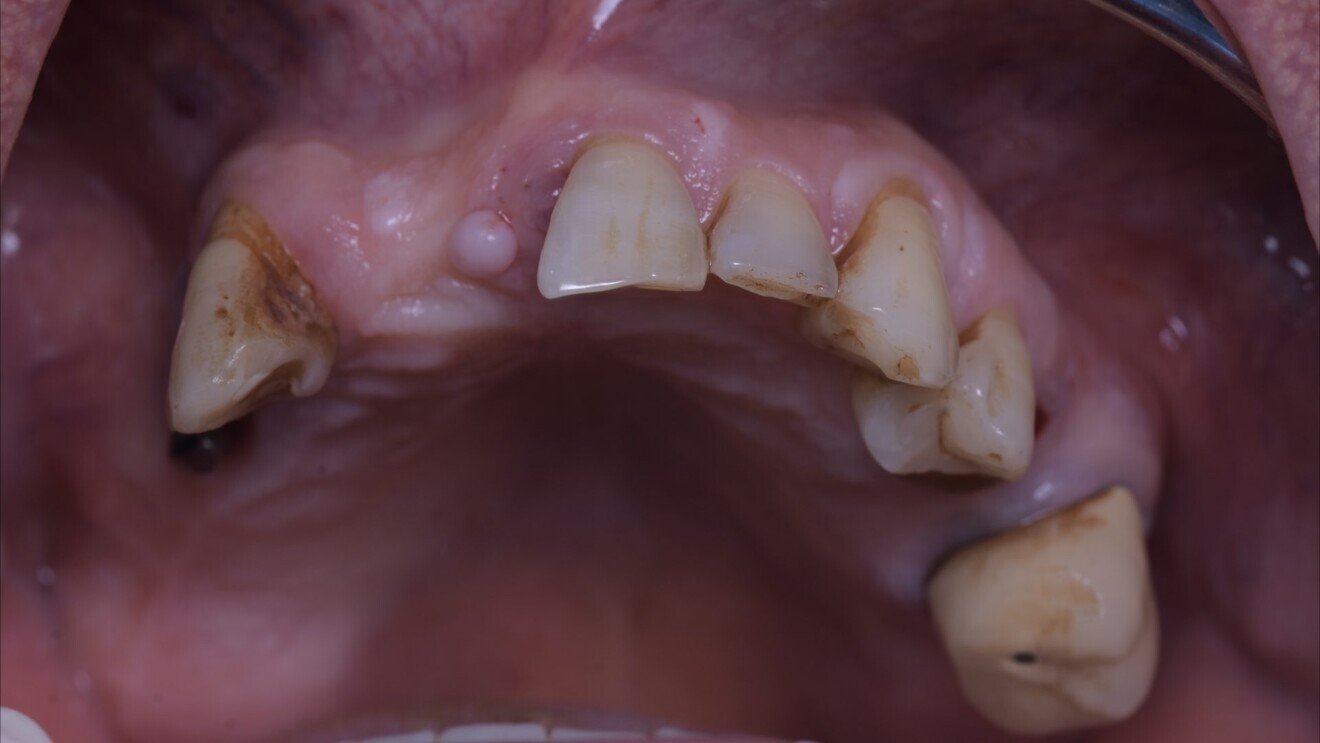

À ce stade-là (Fig. 13), les particules de comblement de GTO (comblement xénogénique), utilisées afin de combler les alvéoles maxillaires, sont encore présentes dans l’épaisseur gingival car elles ne sont pas encore intégrées aux tissus mous, mais la mise en condition gingivale guidée par le design et la compression du bridge provisoire, permettent déjà un aménagement idéal pour la réalisation de la prothèse définitive à venir.